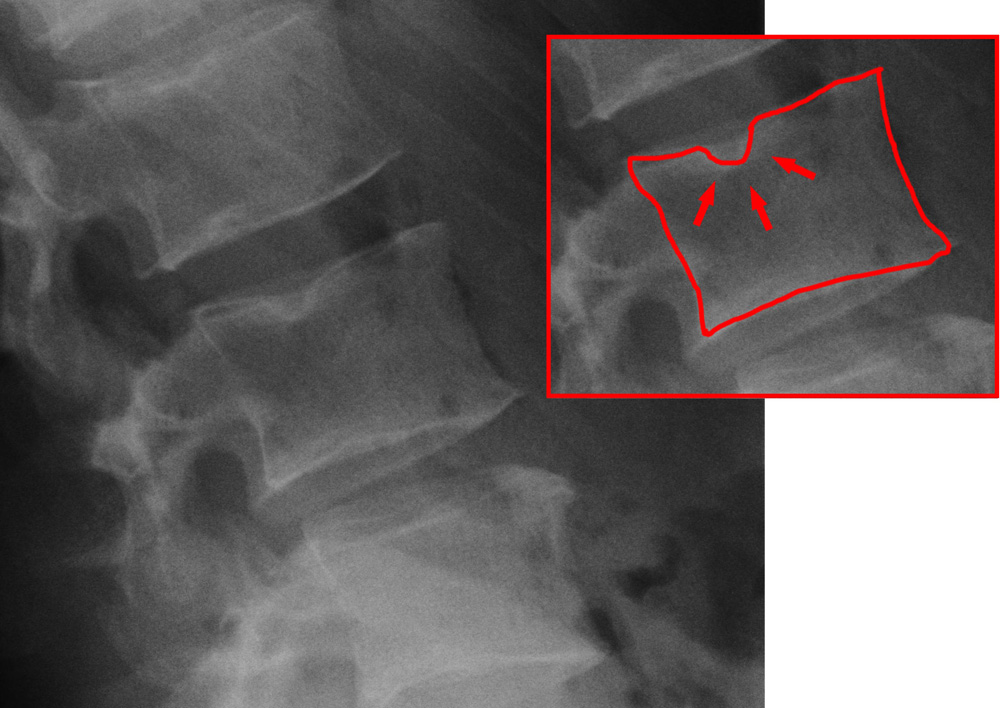

Рентген, МРТ, комп’ютерна томографія — і всі карти розкриті. Тут лікарі застосовують усю гаму технологій! Рентген визначає, коли ви не підозрюєте ніяких неприємностей, проте вже маєте вузли.